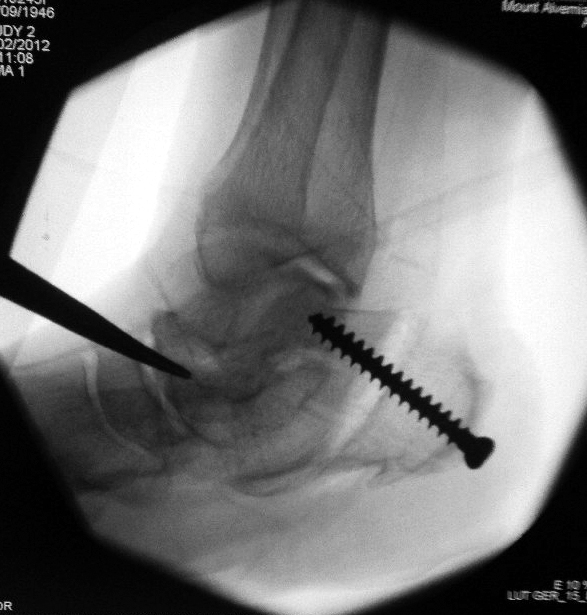

Fluoroscopy in the operating room shows correct placement of a single fixation screw into the heel bone.